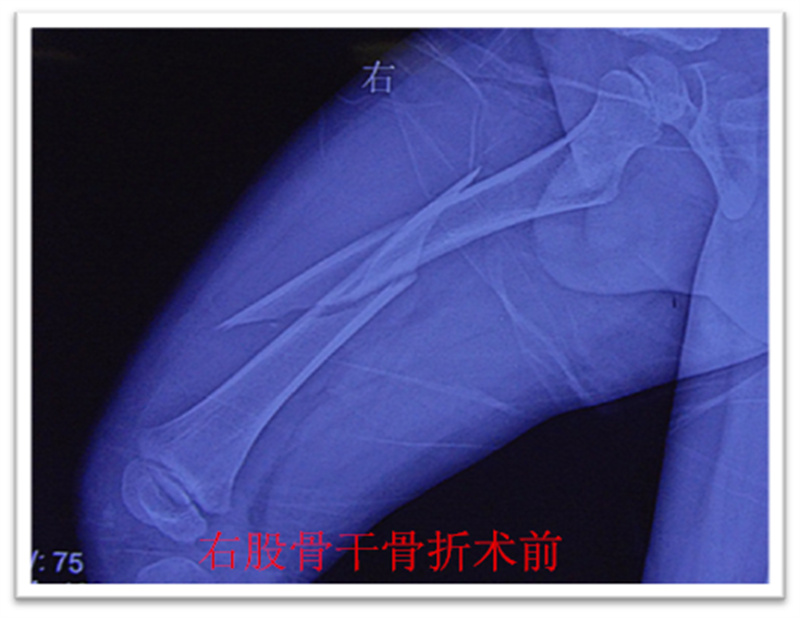

,弹性髓内钉内固定解决了这个矛盾。有人说,弹性髓内钉的出现是上天对儿童的恩惠。的确,弹性髓内钉是治疗小儿长管状骨骨骨折的一种理想、可靠的内固定方法。弹性髓内钉技术发源于法国,在欧洲广泛应用后,现已为全球所接受,被称为是儿童骨科界的一次革命。徐州儿童医院骨一科应用弹性髓内钉技术治疗四肢长管状骨骨折,具有创伤小、恢复快、并发症相对少,孩子能较快恢复正常生活、学习等优点。该技术先将骨折闭合复位,通过微小的切口将特制的弹性髓内钉置入骨髓腔,达到固定骨折的目的。适用于肱骨,股骨,尺桡骨等部位的常见骨折。